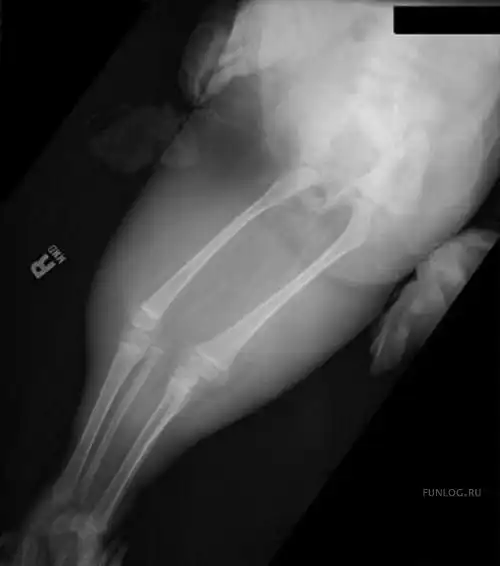

Большинство детей с «сиреномелией» - редким врожденным пороком развития – так называемым «синдромом русалки» погибают в первые часы после появления на свет из-за многочисленных сопутствующих дефектов развития…В настоящее время в мире известны три случая спасения детей с подобным синдромом – это американка Тифани Йоркс, успешно перенесшая операцию по разделению ног 19 лет назад,трехлетняя перуанская девочка Милагрос Серрон, последняя операция по разделению ног которой была проведена летом этого года, и Шилох Пепин, единственная, кого так и не прооперировали…

Кроме сросшихся ног у девочки при рождении не досчитались мочевого пузыря, матки, толстого кишечника, влагалища…У неё была лишь одна недоразвитая почка и один яичник…

Серьезной проблемой было отсутствие так называемых вертлюжных впадин - суставных ямок для бедер - без них девочка не смогла бы стоять. Однако выяснилось, что постепенно ее скелет сформировал нужные части…